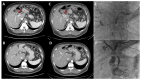

Perihilar cholangiocarcinoma is a rare hepatobiliary malignancy that requires thoughtful, multidisciplinary evaluation in the preoperative setting to ensure optimal patient outcomes. Comprehensive preoperative imaging, including multiphase CT angiography and some form of cholangiographic assessment, is key to assessing resectability. While many staging systems exist, the Blumgart staging system provides the most useful combination of resectability assessment and prognostic information for use in the preoperative setting. Once resectability is confirmed, volumetric analysis should be performed. Upfront resection without biliary drainage or portal venous embolization may be considered in patients without cholangitis and an estimated functional liver remnant (FLR) > 40%. In patients with FLR < 40%, judicious use of biliary drainage is advised, with the goal of selective biliary drainage of the functional liver remnant. Percutaneous biliary drainage may avoid inadvertent contamination of the contralateral biliary tree and associated infectious complications, though the relative effectiveness of percutaneous and endoscopic techniques is an ongoing area of study and debate. Patients with low FLR also require intervention to induce hypertrophy, most commonly portal venous embolization, in an effort to reduce the rate of postoperative liver failure. Even with extensive preoperative workup, many patients will be found to have metastatic disease at exploration and diagnostic laparoscopy may reduce the rate of non-therapeutic laparotomy. Management of perihilar cholangiocarcinoma continues to evolve, with ongoing efforts to improve preoperative liver hypertrophy and to further define the role of transplantation in disease management.